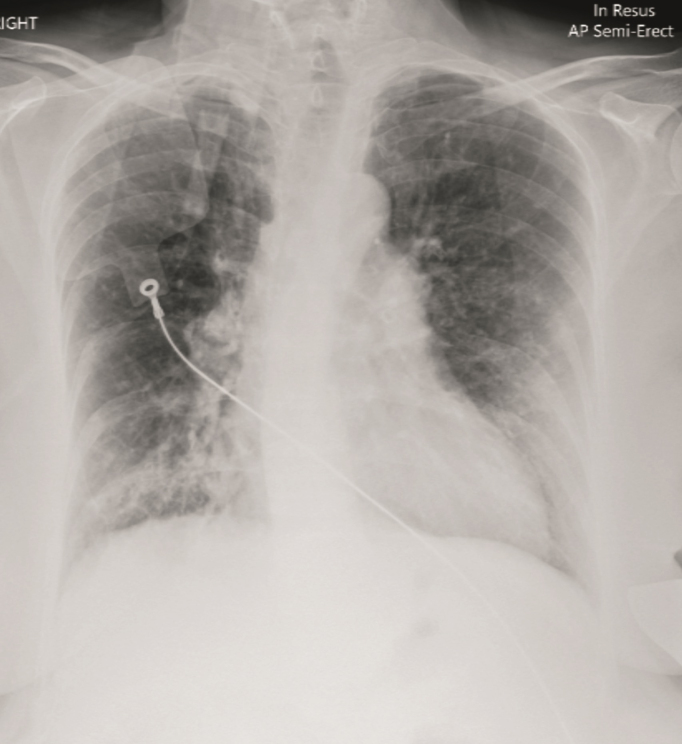

Case presentation: Hereby we describe a 53-year-old patient with severe uncontrolled asthma who presented with chronic hypercapnic respiratory failure. During her medical workup, she was noted to have several comorbidities leading to her respiratory failure. The patient had radiological evidence of bronchiectasis with recurrent episodes of infection, and a severe deformity of the spine due to Kyphoscoliosis. Probably the kyphotic component of this deformity had worsened due to a long history of oral steroid use leading to severe osteoporosis and consequent vertebral compression fractures reaching a Cobb angle of 73 degrees. This was probably caused by the patient's non-compliance with inhaler therapy and an excessive reliance on oral steroid use. Her respiratory failure was treated with domiciliary noninvasive positive pressure ventilation and 24-hour oxygen therapy and her symptoms improved.